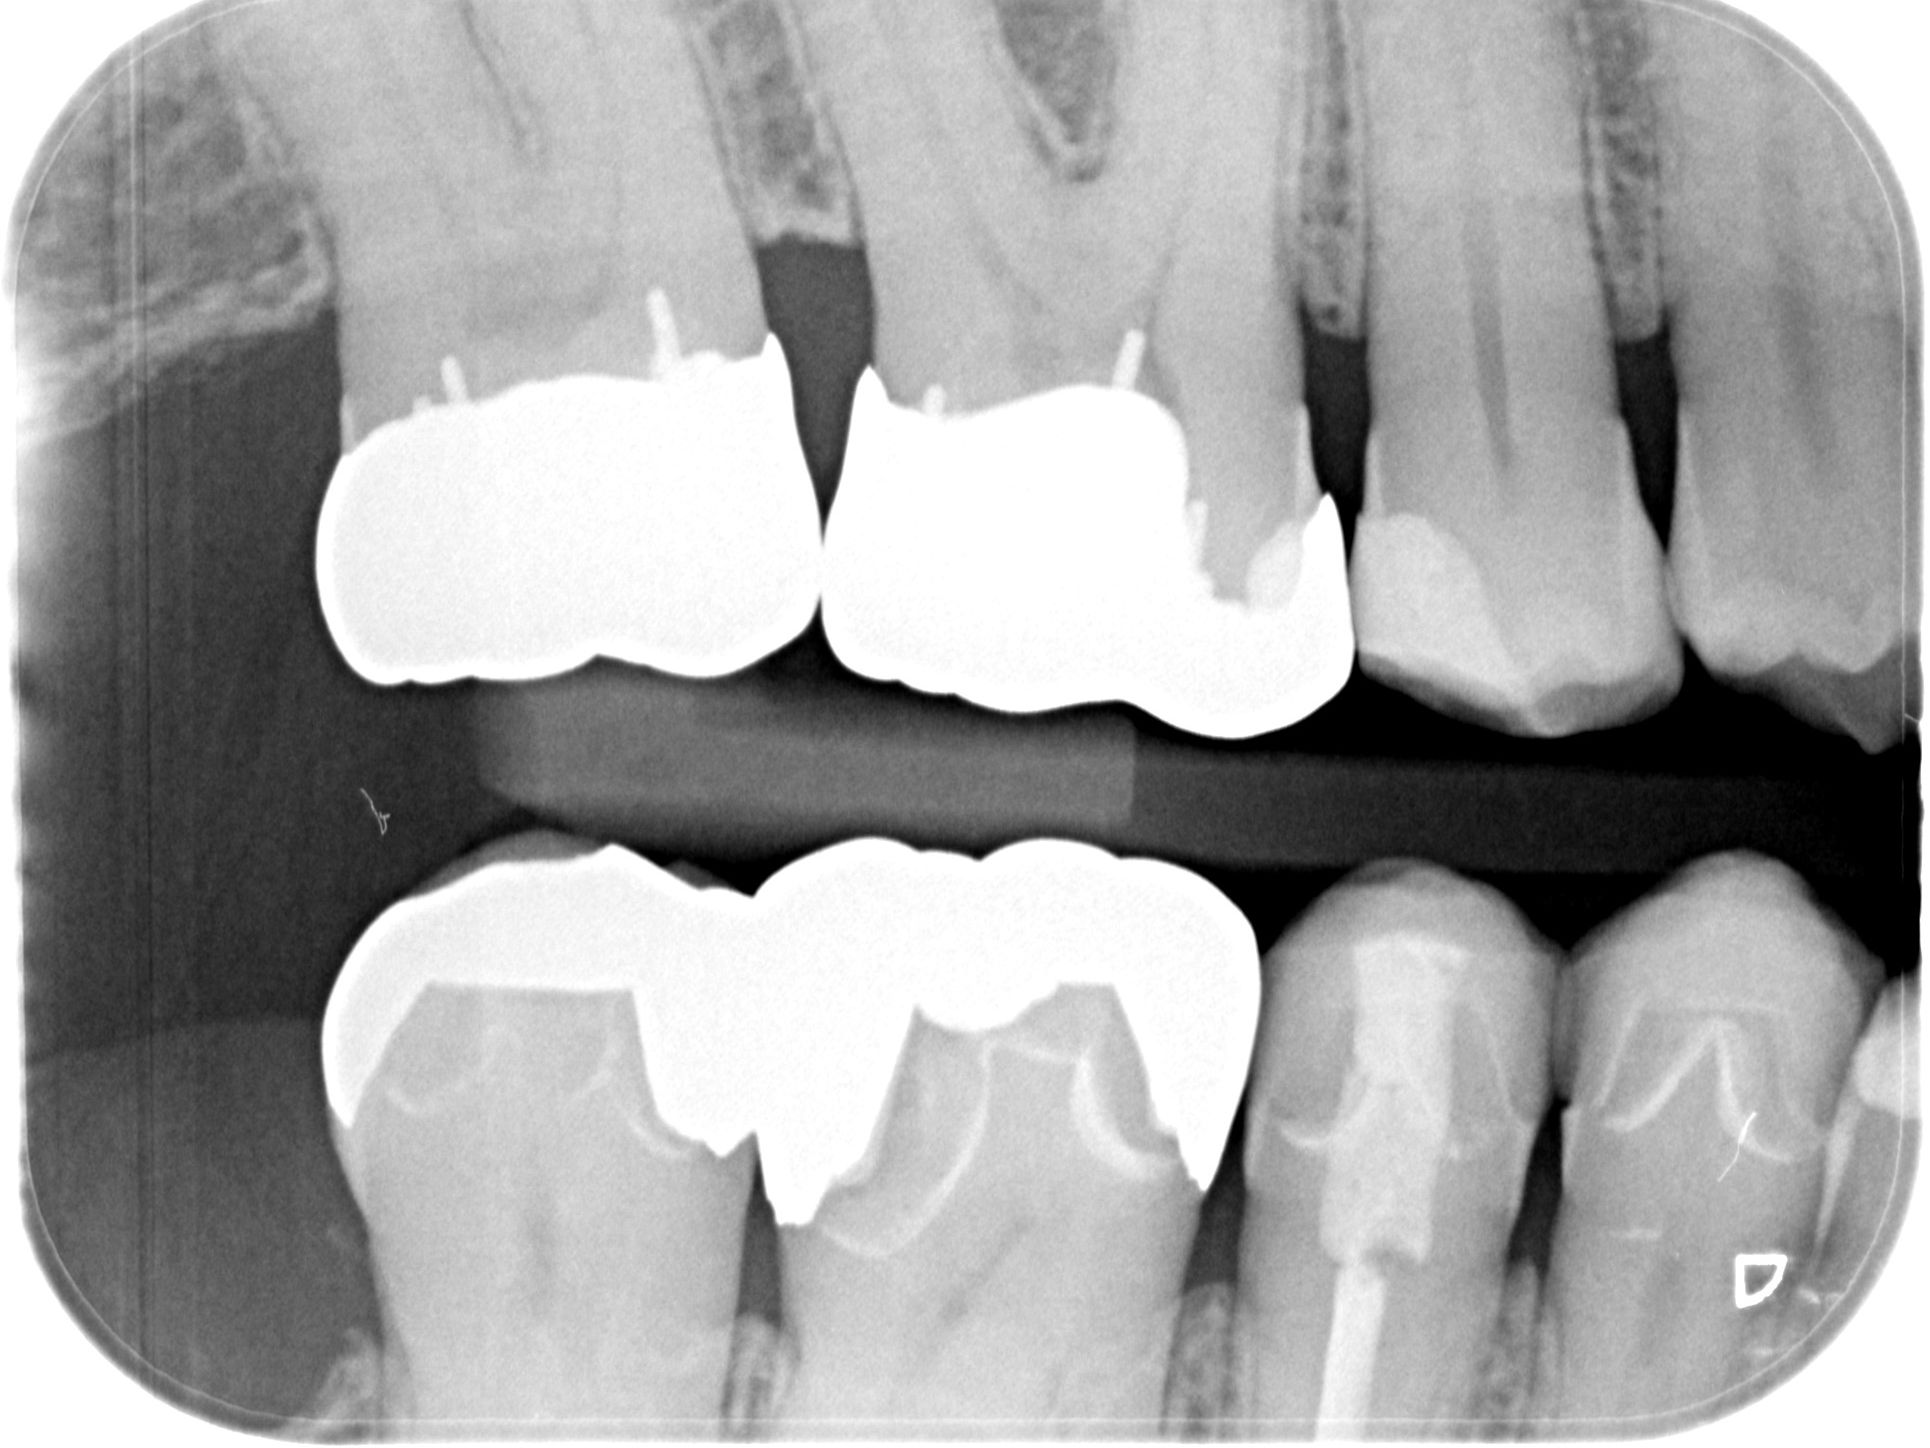

Teilkronen und ein Inlay

Ich bin Herrn Dr. xxx sehr dankbar. Er hat sich meine Zähne angeschaut und die mitgebrachten Röntgenbilder. Er war total begeistert von meinen alten Kronen und hat mir versichert, dass daran überhaupt nichts gemacht werden muss. Unfassbar, dass mir ein anderer Zahnarzt alles erneuern wollte.